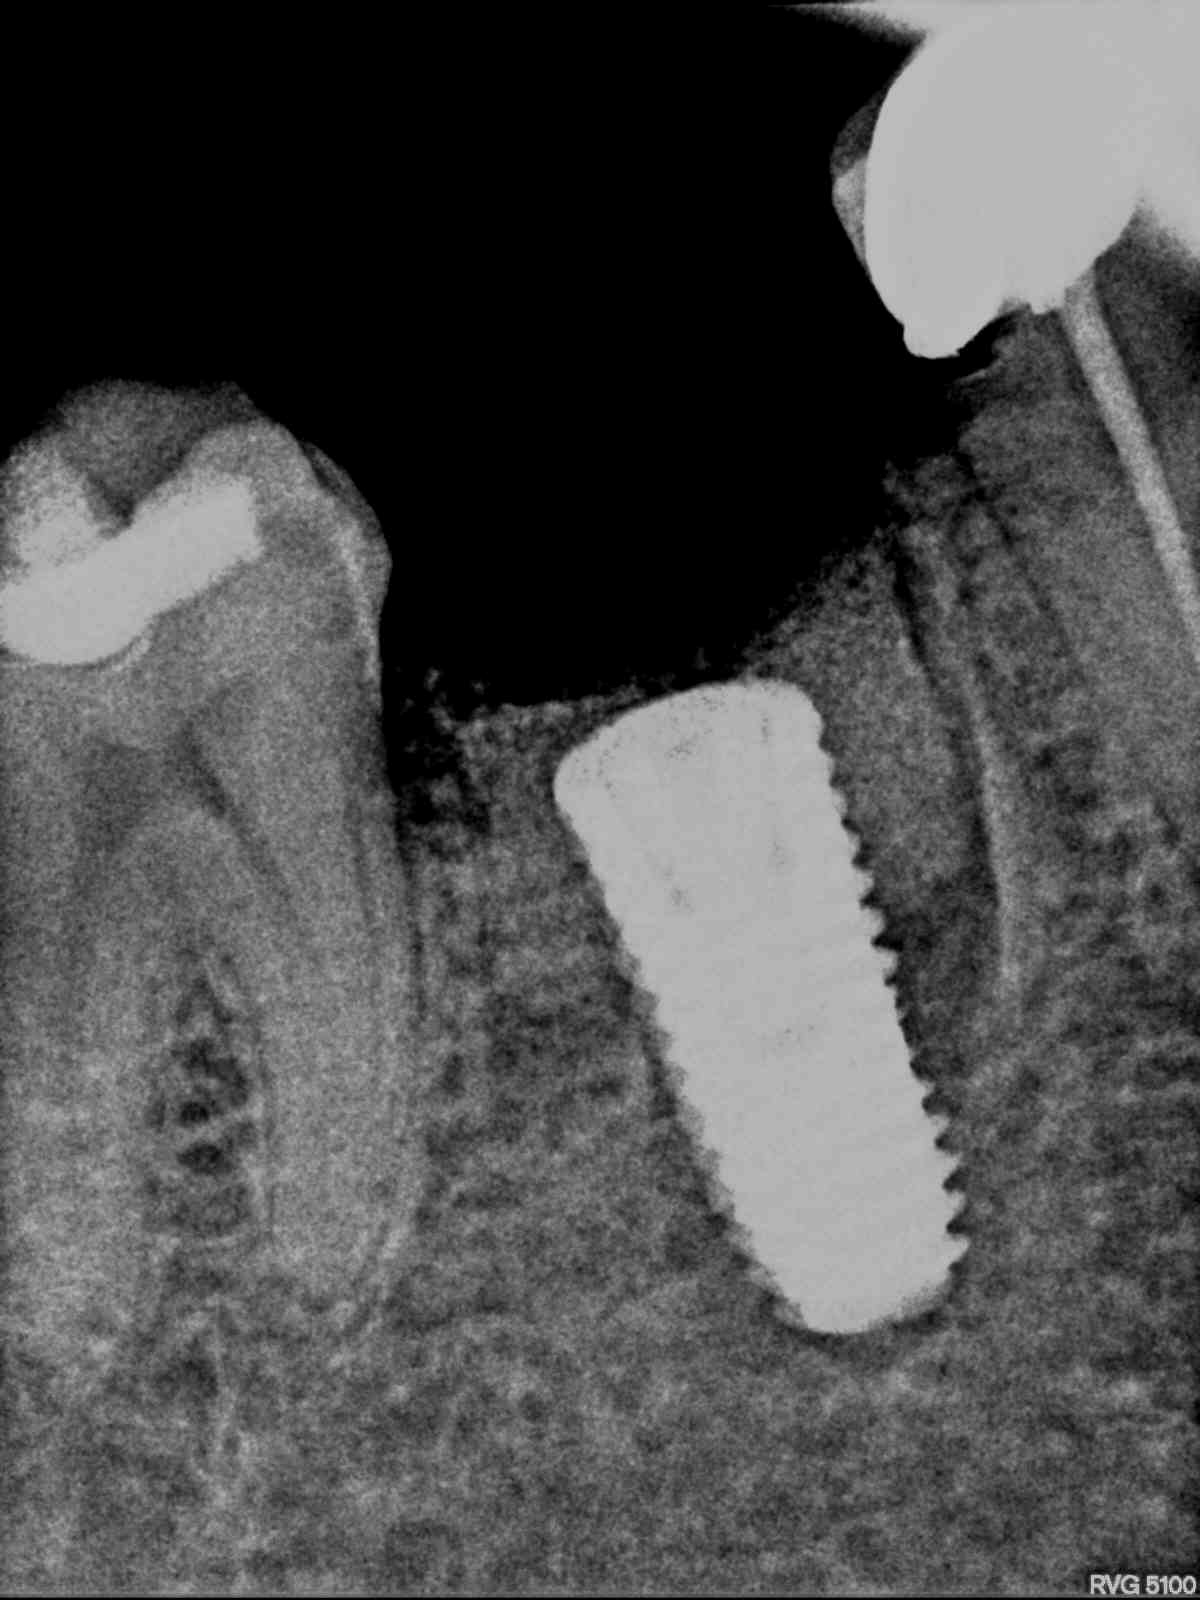

Extraction followed by immediate implant placement along grafting the Jump space. SCRP prosthesis was given finally. 1 Year follow up is also there.